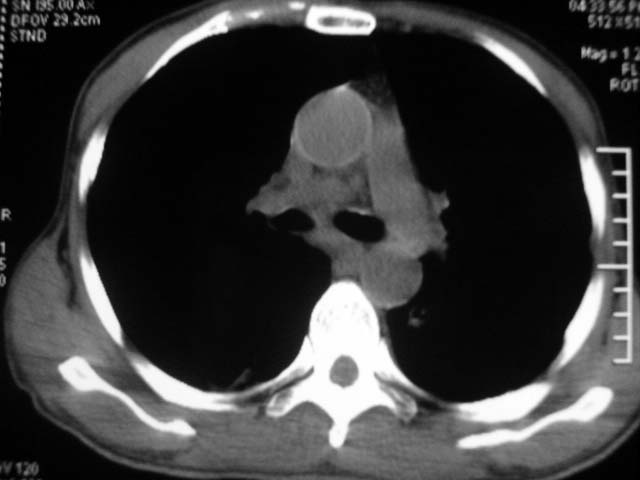

男,52岁,发热2月,糖尿病史。

抗结核治疗irpz方案,血糖未治疗,空腹15.9左右。症状无好转,左胸痛。

复查ct

2、双肺见多发片状及结节状高密度影,大多数病灶中心均见“空泡征”。

3、纵隔内淋巴结肿大。

结果:两肺继发性肺结核并曲霉菌感染。